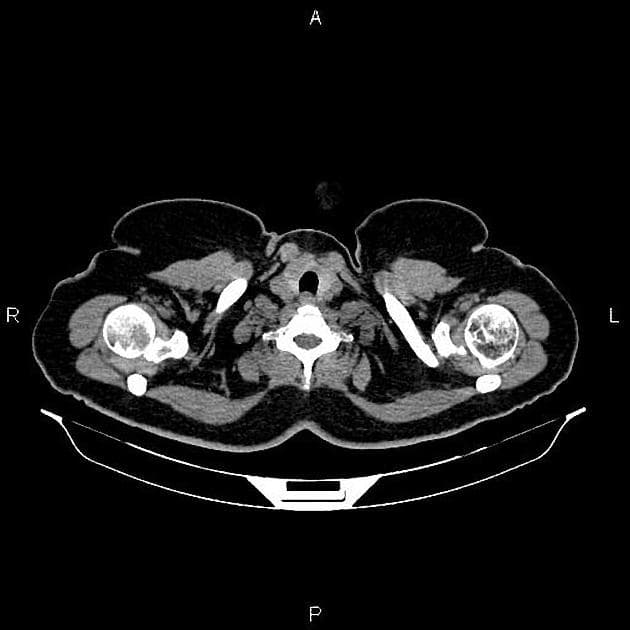

Axial C+ portal venous phase

- Cắt ngang CT qua thận cho thấy tổn thương giảm tỷ trọng ở thận trái, đặc điểm của mô mỡ, kèm theo tụ dịch quanh thận, nhiều khả năng là máu.

- Hình ảnh này phù hợp với u mạch cơ mỡ thận chảy máu (bleeding angiomyolipoma).

- Không thấy bằng chứng của các tổn thương khác gây chảy máu khoảng sau phúc mạc.